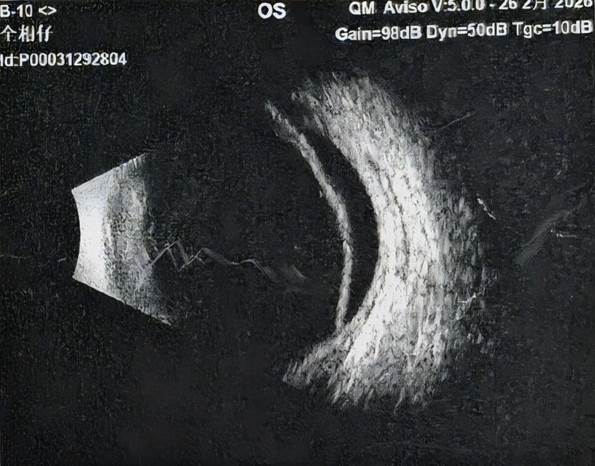

△术前视网膜脱离(左图)与术后复位(右图)

患者入院时病情极为危急,左眼视物变形且模糊,视网膜脱离范围已累及黄斑区,若延误治疗,将面临永久性失明风险。南华医院眼科团队联合多维度眼底探查,反复比对影像数据,最终精准锁定隐匿性视网膜裂孔,确诊为复杂性孔源性视网膜脱离,为手术制定了科学方案。

手术过程中,医护团队全程给予患者心理疏导与细致关怀,缓解其紧张情绪,全程操作精准轻柔,最大程度减少眼部损伤。术后,患者恢复效果远超预期,次日视物变形、模糊症状即有明显好转,一周后复查显示视网膜完美贴附复位,且无任何不适症状。目前,患者已顺利出院,后续随访眼部状况持续向好,彻底摆脱了失明的危机。